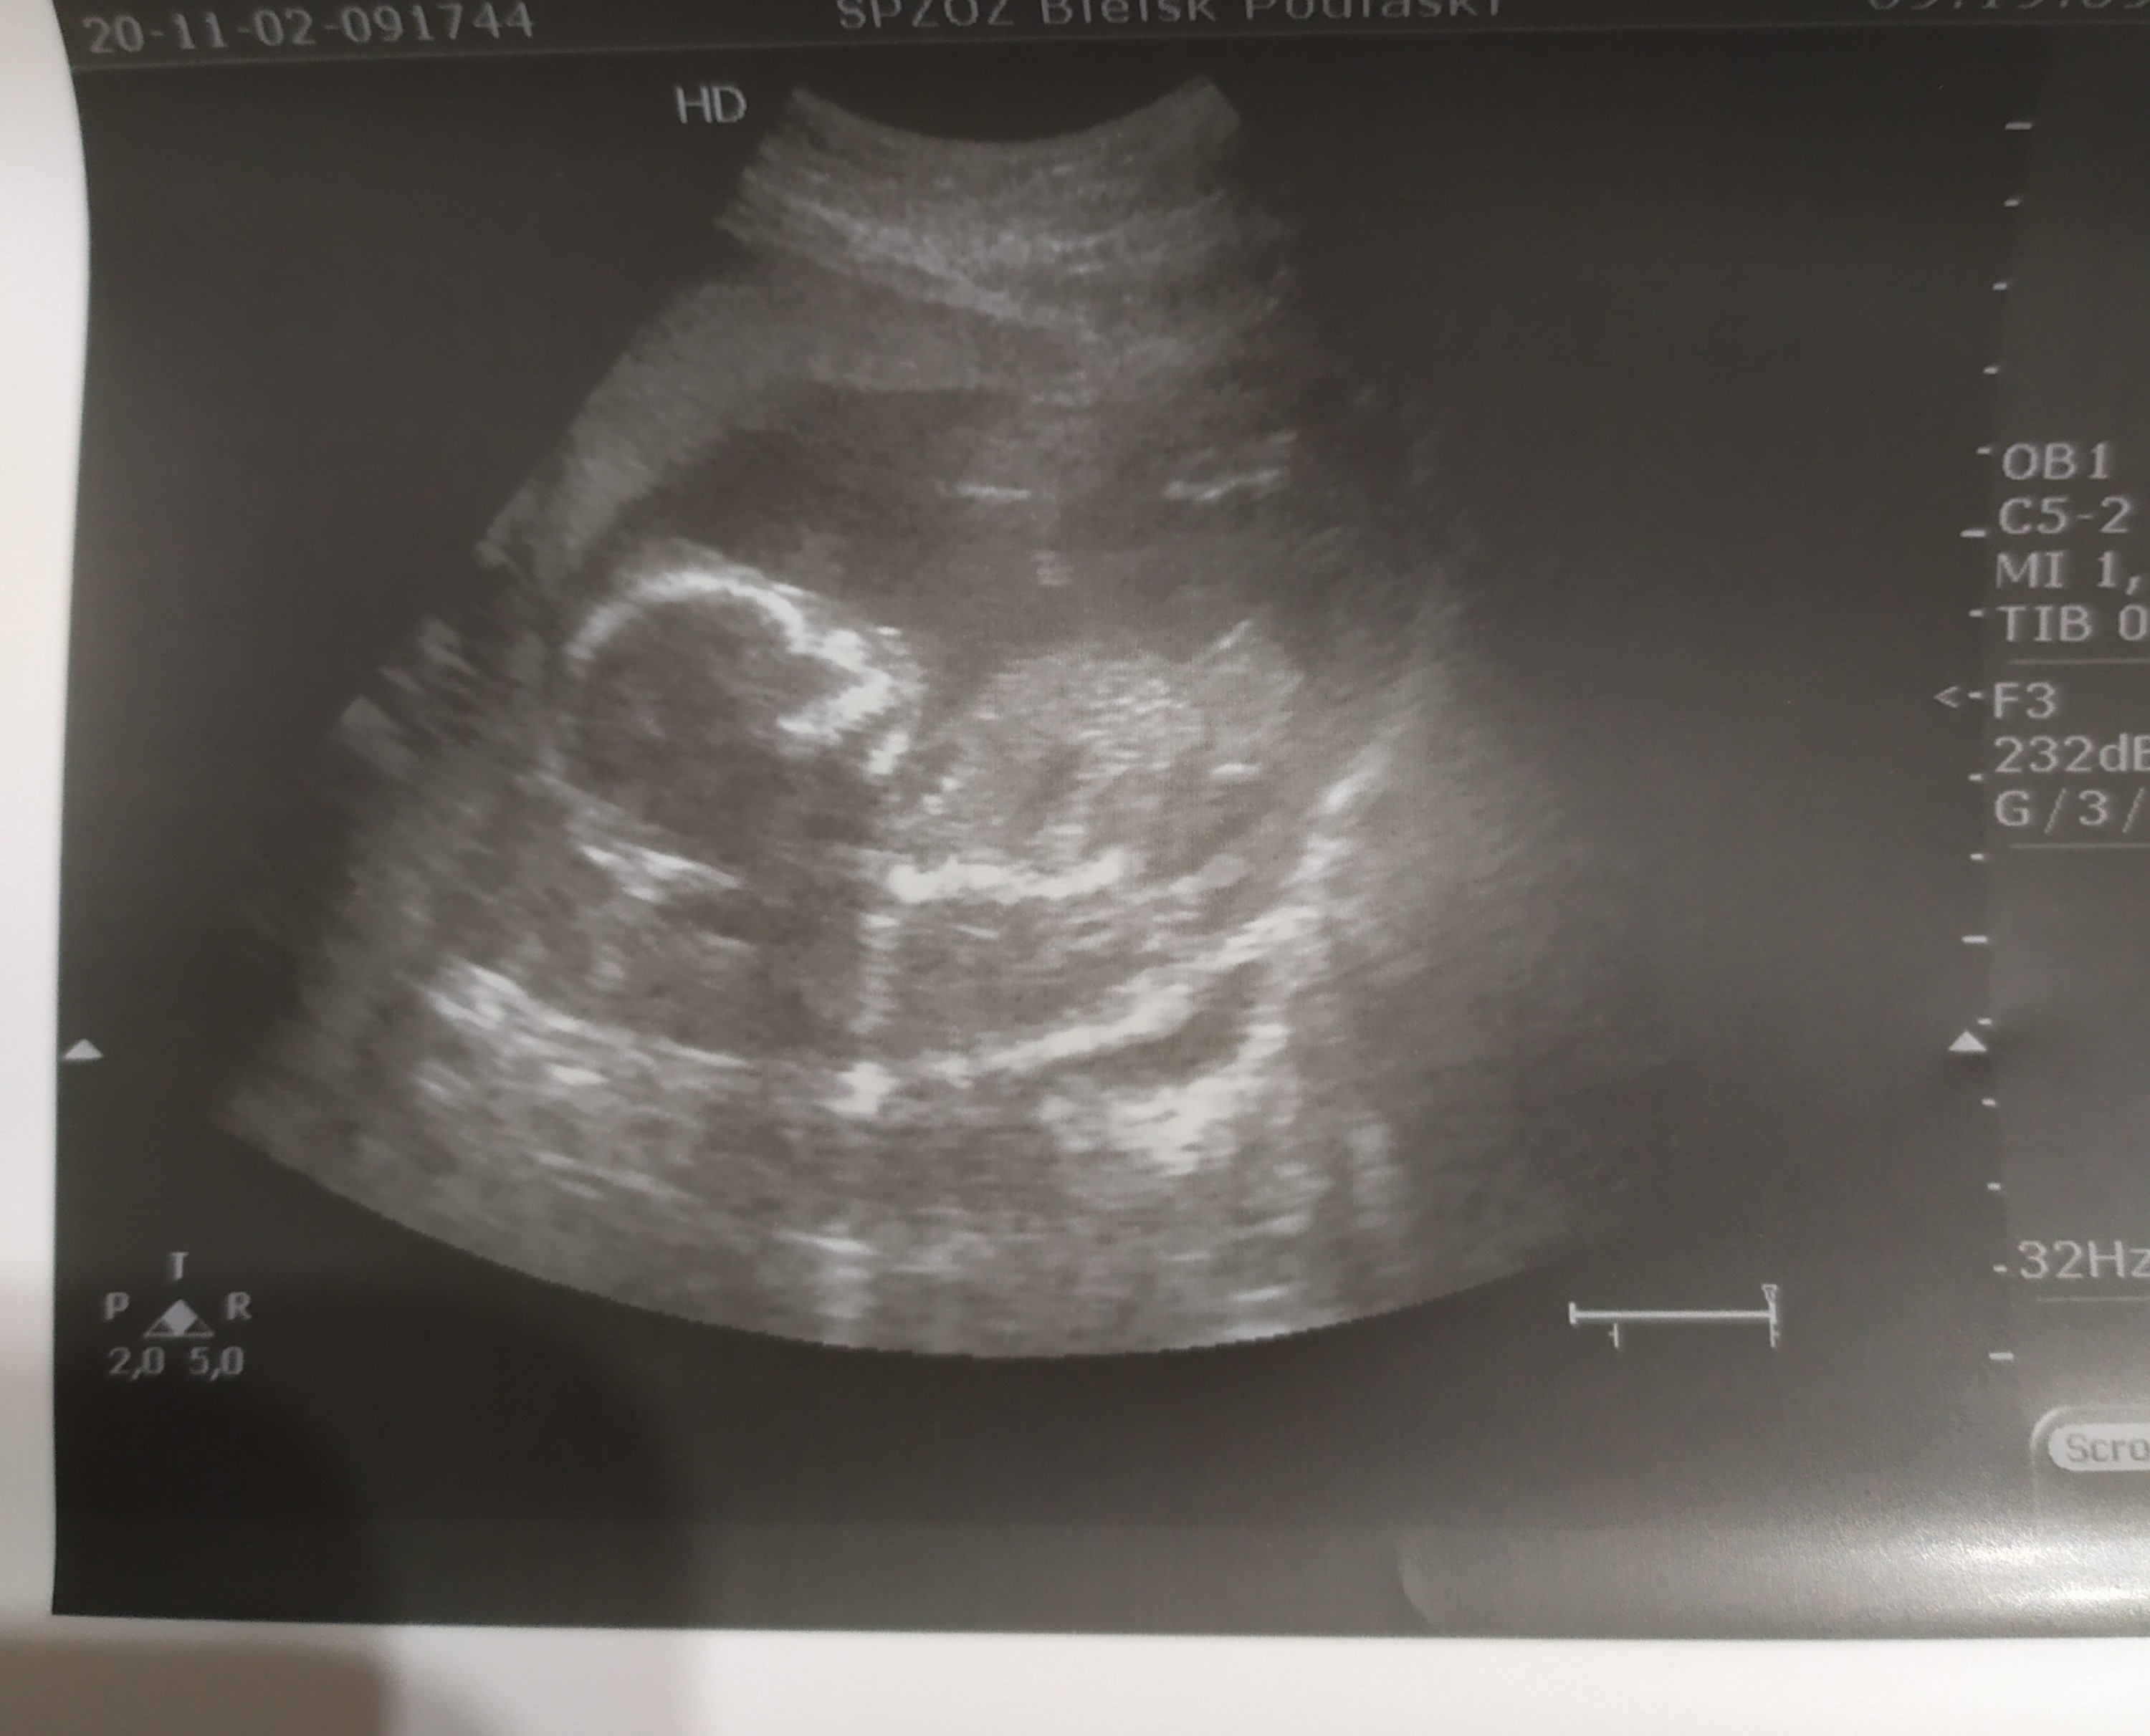

Hahaha mój też dostał specjalne zdjęcie, które oczywiście rozesłał po kolegach, by się pochwalićto tak jak u mnie. Mały tak genitalia wywalił ze lekarz się śmiał i wydrukował zdjęcie dla męża